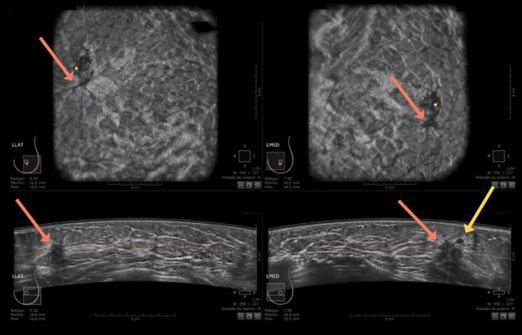

- ABUS: Ngoài khối u trên còn phát hiện thêm một khối giảm âm không đều, có gai nằm ngay phía sau - BI-RADS 4

Hình 9. Khối giảm âm, bờ rõ quan sát thấy trên ABUS (mũi tên vàng) và khối giảm âm, bờ không đều và có tua gai nằm ngay phía sau (mũi tên cam) – BI-RADS 4

Kết quả mô bệnh học: Sẹo hình tia (Radial scar)

Ý nghĩa lâm sàng: Với lát cắt và mặt phẳng quan sát đặc trưng (ví dụ coronal view) dày 2mm, ABUS cung cấp “bản đồ” cấu trúc mô vú rõ ràng hơn, giúp nhận diện các biến đổi kiến trúc mà siêu âm 2D đôi khi khó thể hiện trọn vẹn.